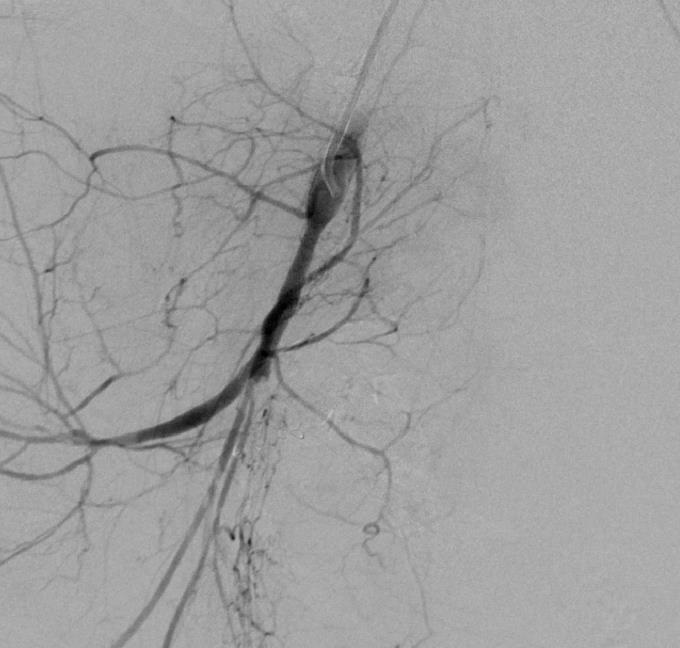

末端动脉阻塞(end-artery occlusion)

末端动脉栓塞:医源性肾损伤-移植肾活检

活检后动脉瘤破裂 |

微导管在载瘤动脉末端 |

载瘤动脉末端栓塞 |

Coil=3 |

直接动脉末端栓塞的过程是简单推出弹簧栓子(simply pushed out coil),但要求弹簧栓子的直径≥血管直径